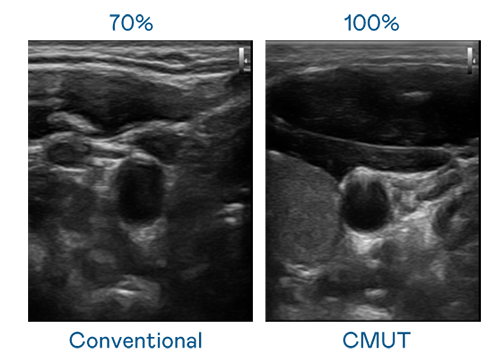

CMUT 技术是一种用电容式微机电元件来产生超音波讯号的技术。与传统 PZT 压电式技术相比,CMUT 频宽增加 30%,更宽频的超音波讯号让影像解析度大幅提升,是实现高影像品质医疗超音波扫描、促进精准医疗发展的关键技术。

超音波影像的解析度高低,首先取决于探头能发出的讯号频宽。evo视讯 CMUT 可提供高清晰的超音波讯号,提供高频宽、高灵敏度、影像纹理细节更高的超音波影像,协助医护人员缩短影像判读时间及利用精准的医疗影像进行诊断。